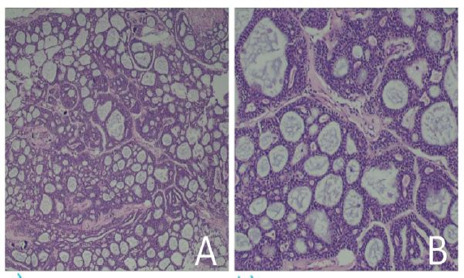

Adenoid cystic carcinoma (ACC) is a rare slow-growing but aggressive malignant tumor arising from the epithelial cells of mucous-secreting glands. Primary intracranial ACC is one of the rarest entity. We report a case of a 61 years old male presenting with difficulty in swallowing, slurring of speech, generalized body weakness. Patient had residual right cerebellopontine angle (CPA) mass causing midline shift and fourth ventricular obstruction on MRI. Patient underwent right retrosigmoid craniotomy with excision of CPA mass. Histopathological examination confirmed the case as primary intracranial ACC.